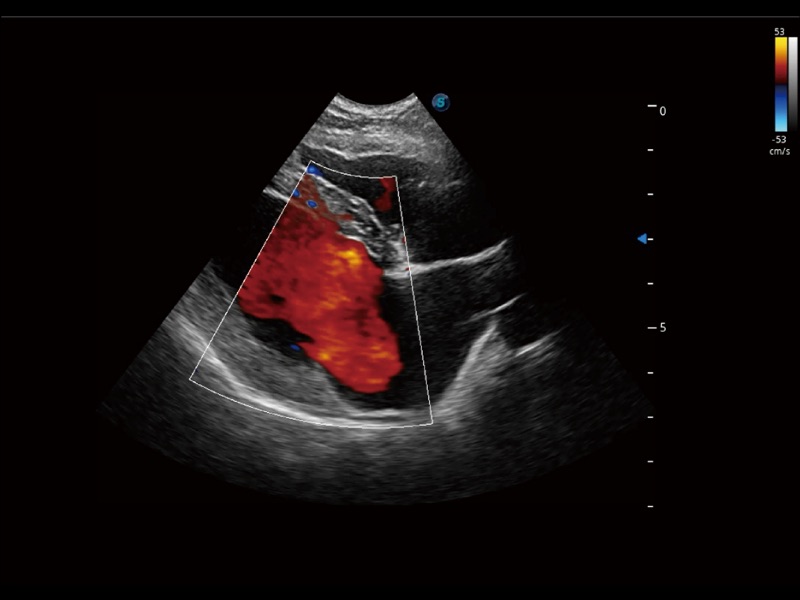

优异的基础图像

ProPet 70 全新的动物超声智能软件和丰富的探头群,为动物医生提供了高清晰度和精细分辨率的图像,无论在宠物、马科、畜牧还是实验室动物等应用中都可以轻松应对,为您的日常工作带来满意的体验。

(犬)左室长轴血流